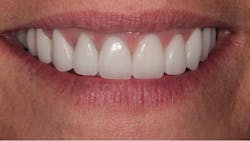

The final result can be seen from the occlusal view in Figure 9 and the retracted facial view in Figure 10. The patient’s new smile can be seen in Figure 11. Utilizing IPS e.max crowns and veneers, we were able to enhance the patient’s smile by creating a lighter color and a wider, more attractive look.

Figure 11: The patient’s new smile